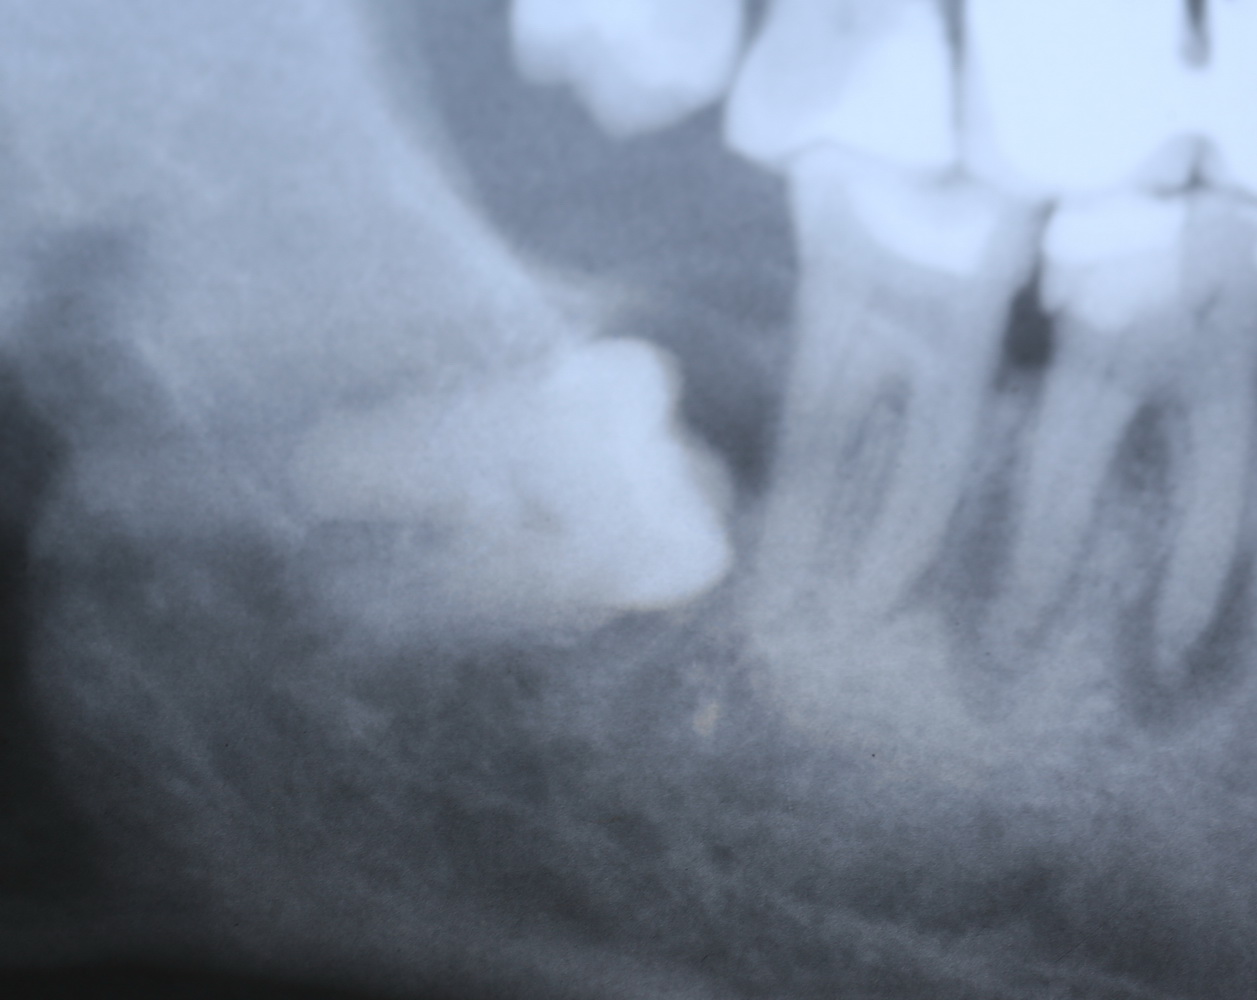

У моей пациентки случайно мы обнаружили два ретинированных сверхкомплектных премоляра:

При этом, весь комплект зубов на месте (за исключением правой верхней восьмерки — моя работа).

Вот разбор снимка:

Давайте еще раз посмотрим на снимок:

Что мы на нем видим? Ну да, есть два лишних зуба.

Но…

К сожалению, мы не можем по ортопантомограмме…

- … достоверно определить положение зубов. Ортопантомограмма искажает.

- …определить их отношение к нижнечелюстному каналу и соседним зубам. Они находятся ближе к щеке или языку? Нижнечелюстной канал проходит за, между или перед ними? Мы должны ОБЯЗАТЕЛЬНО знать ответы на эти вопросы.

- … самое главное — спланировать операцию в целом и схему операционного доступа, в частности! Это важно? Еще как!

Кстати, по этим же причинам НЕЛЬЗЯ планировать операцию имплантации или остеопластики, основываясь на данных панорамного снимка. Всегда-всегда перед сложным лечением нужно делать компьютерную томографию.

Что, собственно, мы и делаем:

По-моему, на скриншоте всё понятно. Зубы, которые нужно удалить нафиг, обозначены белой стрелкой и словосочетанием «удалить нафиг!«. Темным пунктиром обозначены контуры зубов. Черная точка — просвет нижнечелюстного канала. Снизу слева я попытался наглядно показать схему взаимного расположения и отношения сверхкомплектных зубов к нижнечелюстному каналу. Ну и, внимательно изучив КТ, я принял решение, что операционный доступ нужно делать с язычной стороны.